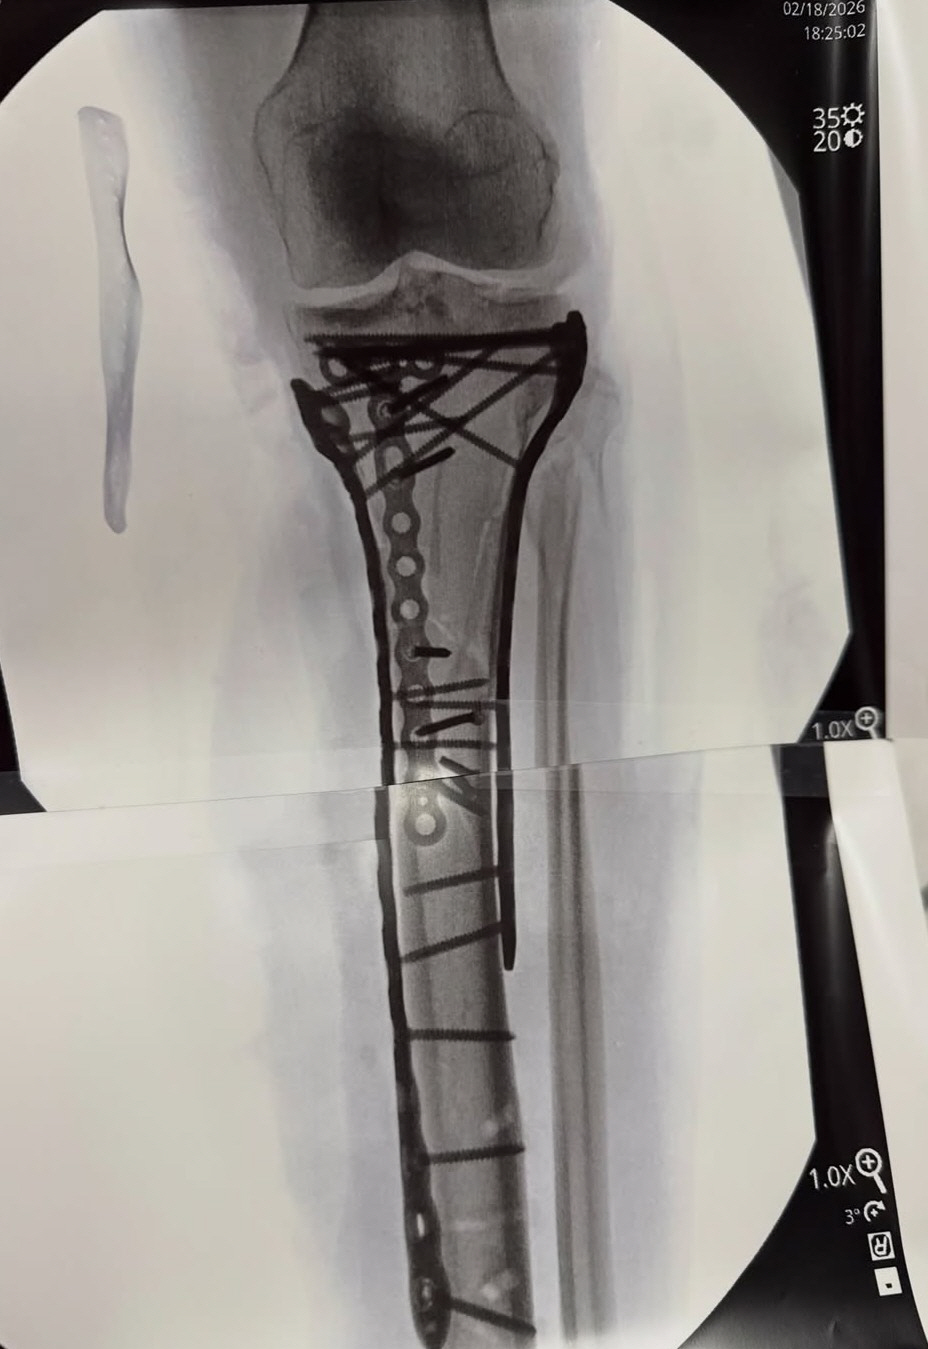

이탈리아에서 4차례나 수술대에 오른 후 미국으로 돌아간 본은 21일 5차 수술을 받았다. 그는 수술 후 병상에 누워 이동하는 영상과 함께 금속판과 나사가 박힌 엑스레이 사진을 공개했다.